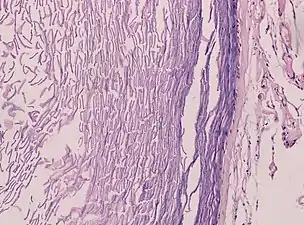

- Histopathology, showing a keratinizing stratified squamous epithelium, and a lumen containing keratin flakes

- Histopathology showing epithelium and lamellated keratin (left)